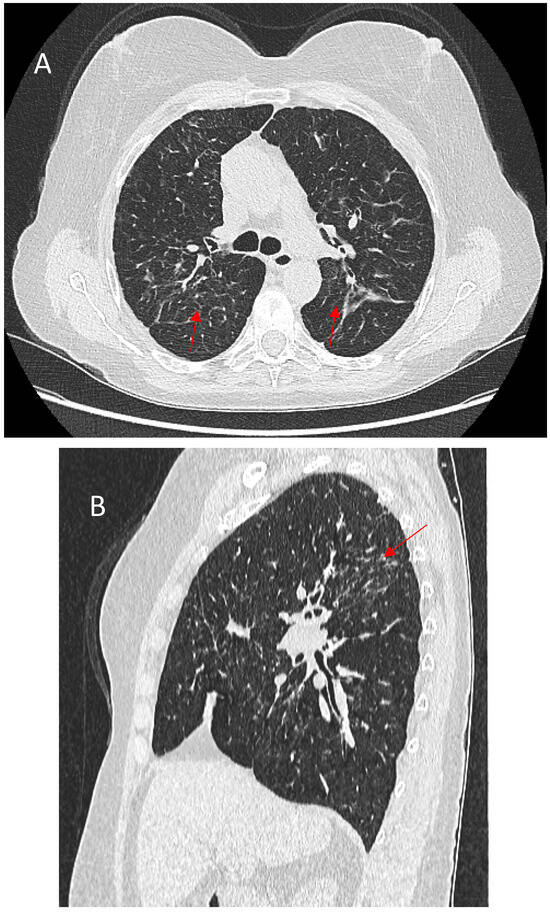

5.1.1. Micronodules and Ground-Glass Opacities (GGOs)

5.1.4. Linear Fibrosis